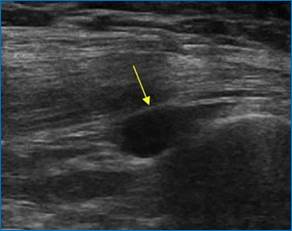

Помимо жидкостного компонента различной эхоплотности могут быть выявлены хондроматозные включения в полости, в просторечьи «суставные мыши» (рис.2).

Рис. 2. Хондроматозное включение в полости сустава